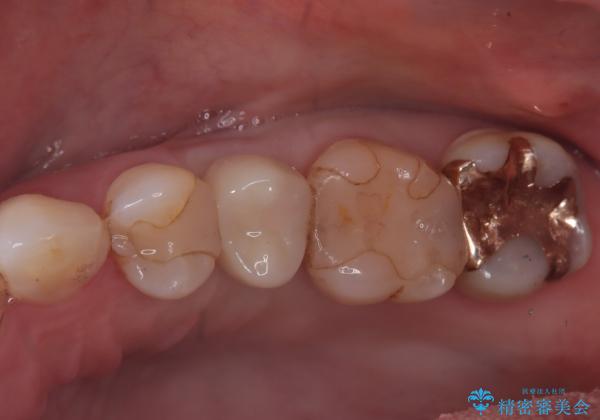

- 根管治療をしている歯が破折し、抜歯となってしまいました。

抜歯した部位に対して、はじめに可撤性部分義歯,ブリッジ、インプラントによる治療方法とそれぞれの利点と欠点について説明を行った結果、インプラント治療を希望されました。さらに、インプラント治療の術前・術後口腔内管理の重要性、手術内容,費用などを説明し、十分なインフォームド・コンセントを得たうえで治療を開始しました。